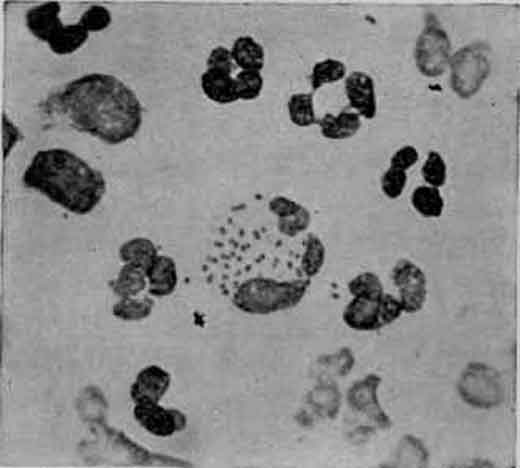

Meningococcus